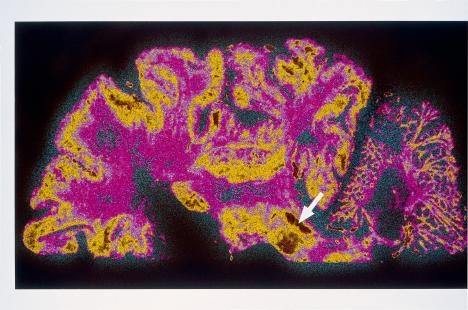

Crédit photo : (c) BSIP 1999 #1872899